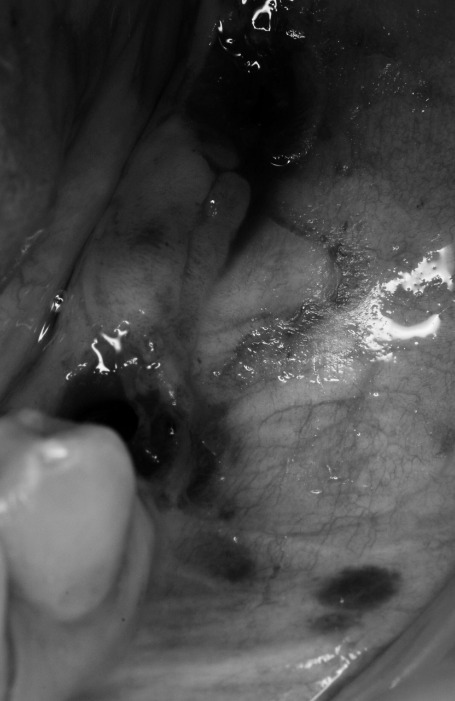

En este caso clínico, realizado por el Dr. Arturo Sánchez Colodro, se ha implementado un injerto mixto de tejido conectivo y gingival junto con cirugía plástica periodontal para mejorar significativamente los resultados en implantes dentales. Gracias a esta técnica avanzada, se logra aumentar el volumen de encía y la banda de encía queratinizada, lo que incrementa la salud y la longevidad de los implantes en nuestros pacientes.

El procedimiento realizado no solo evita la pérdida de hueso y el sangrado alrededor de los implantes, sino que también permite una mejor higiene oral. Los pacientes pueden cepillar sus coronas sobre implantes sin experimentar dolor, asegurando una limpieza eficaz y cómoda. Estos resultados demuestran el compromiso del Dr. Sánchez Colodro con la excelencia y la innovación en el campo de la implantología dental.